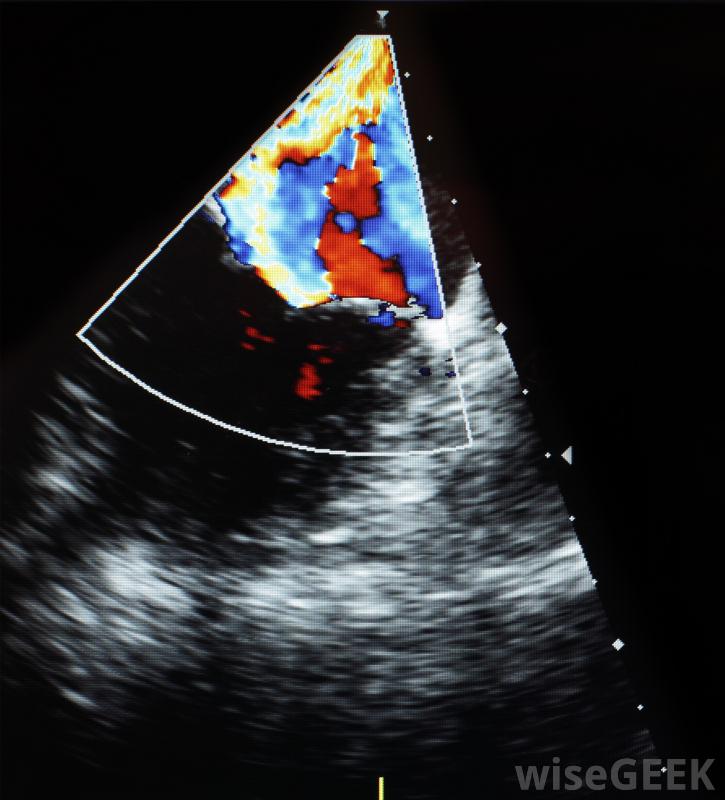

多普勒檢測是一種非侵入性的醫學測試,用于檢查通過大動脈的血流。有時也稱為多普勒超聲,它可以幫助醫生識別可能導致健康并發癥(如中風)的阻塞。多普勒成像也有助于醫生診斷動脈阻塞、血栓,腫瘤和動脈和靜脈的問題。 尼古...

多普勒檢測是一種非侵入性的醫學測試,用于檢查通過大動脈的血流。有時也稱為多普勒超聲,它可以幫助醫生識別可能導致健康并發癥(如中風)的阻塞。多普勒成像也有助于醫生診斷動脈阻塞、血栓,腫瘤和動脈和靜脈的問題。尼古丁會影響多普勒檢測結果。A傳感器是一種手持設備,用于進行測試。傳感器涂有水溶性多普勒凝膠,置于皮膚上方,血管上方。它會發出高頻聲波,在被測靜脈或動脈上反彈。如果血流速度發生變化,聲音的頻率會發生明顯的變化,就像雷達槍測量行駛速度一樣,多普勒測試測量的是血流的速度和效率,如果血流順暢不間斷,則測試正常;如果出現堵塞,多普勒測試結果將返回異常報告多普勒檢測是一種醫學測試,高頻聲波被傳輸到靜脈和動脈以監測血流不正常的結果可能表明各種各樣的問題。一些潛在的問題包括動脈阻塞、靜脈閉合或腫瘤醫生需要解釋多普勒測試結果。警察雷達槍使用多普勒技術多普勒測試在懷孕期間也用于監測血流。從母親到嬰兒的適當流量對嬰兒的健康至關重要。該測試還允許醫生監測和評估嬰兒的心跳。這臺機器實際上可以租給準父母,讓他們在家里進行多普勒測試和傾聽有時進行彩色多普勒超聲檢查,將聲波結果轉換成彩色結果,彩色檢查有時用于識別已識別的癌性腫瘤因為它們通常顯示血流量增加。雖然醫生對這兩種檢查都很在行,彩色版本通常更容易閱讀。多普勒測試幾乎不需要患者準備。患者只需從待測區域脫掉任何衣物。由于尼古丁會影響多普勒測試結果-因為它會導致靜脈收縮,所以病人可能需要在測試前一段時間內禁煙。作為一種非侵入性測試,多普勒測試幾乎不會引起任何不適,也幾乎沒有風險多普勒超聲機利用多普勒效應產生運動圖像。